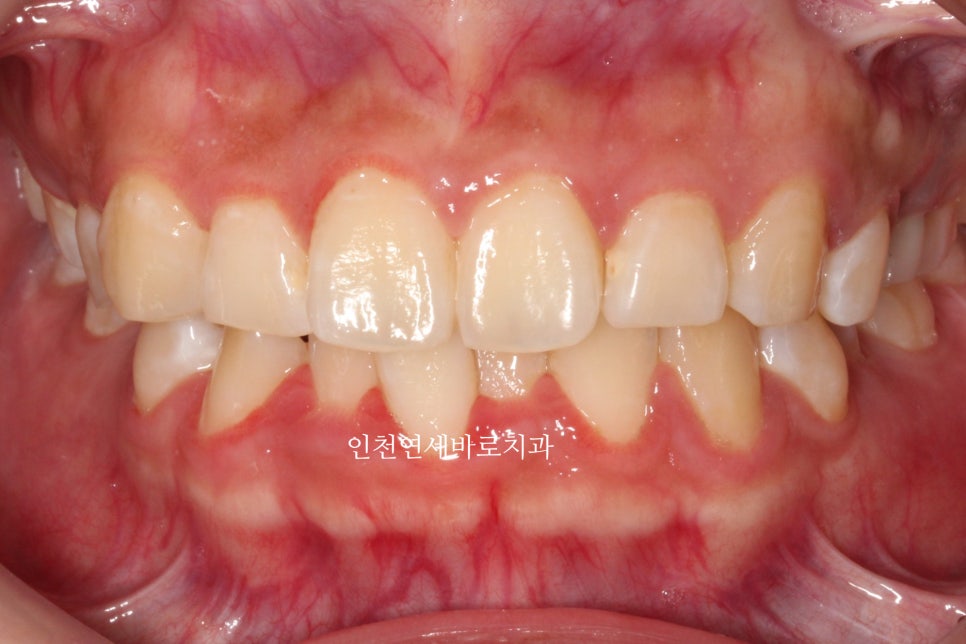

이 환자분의 최종 모습을 일단 먼저 볼께요

재제작했던 두번째 세트까지 모두 마무리 후

임플란트의 머리, 충치치료했던 치아의 크라운까지 모두 치료를 마무리 한 모습입니다.

재제작 전에 비해 정리된 교합을 확인할 수 있죠?